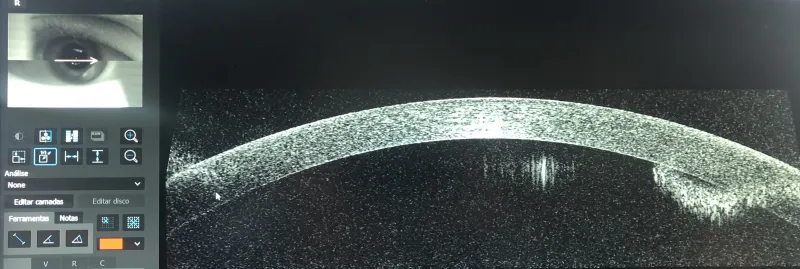

O processo envolve o uso preciso de um laser que remodela a curvatura da córnea, permitindo um melhor foco da visão e reduzindo a dependência de óculos ou lentes corretivas.